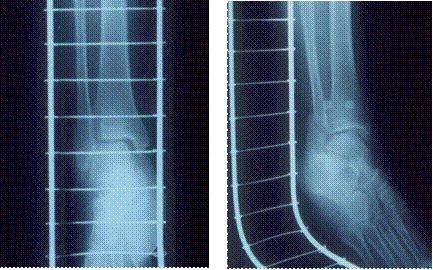

図4 受傷後14日目の受傷部レントゲン写真

左 正面像 腓骨遠位端部の側方転位は改善

右 斜位像 腓骨遠位端部の前後方向の転位が残存